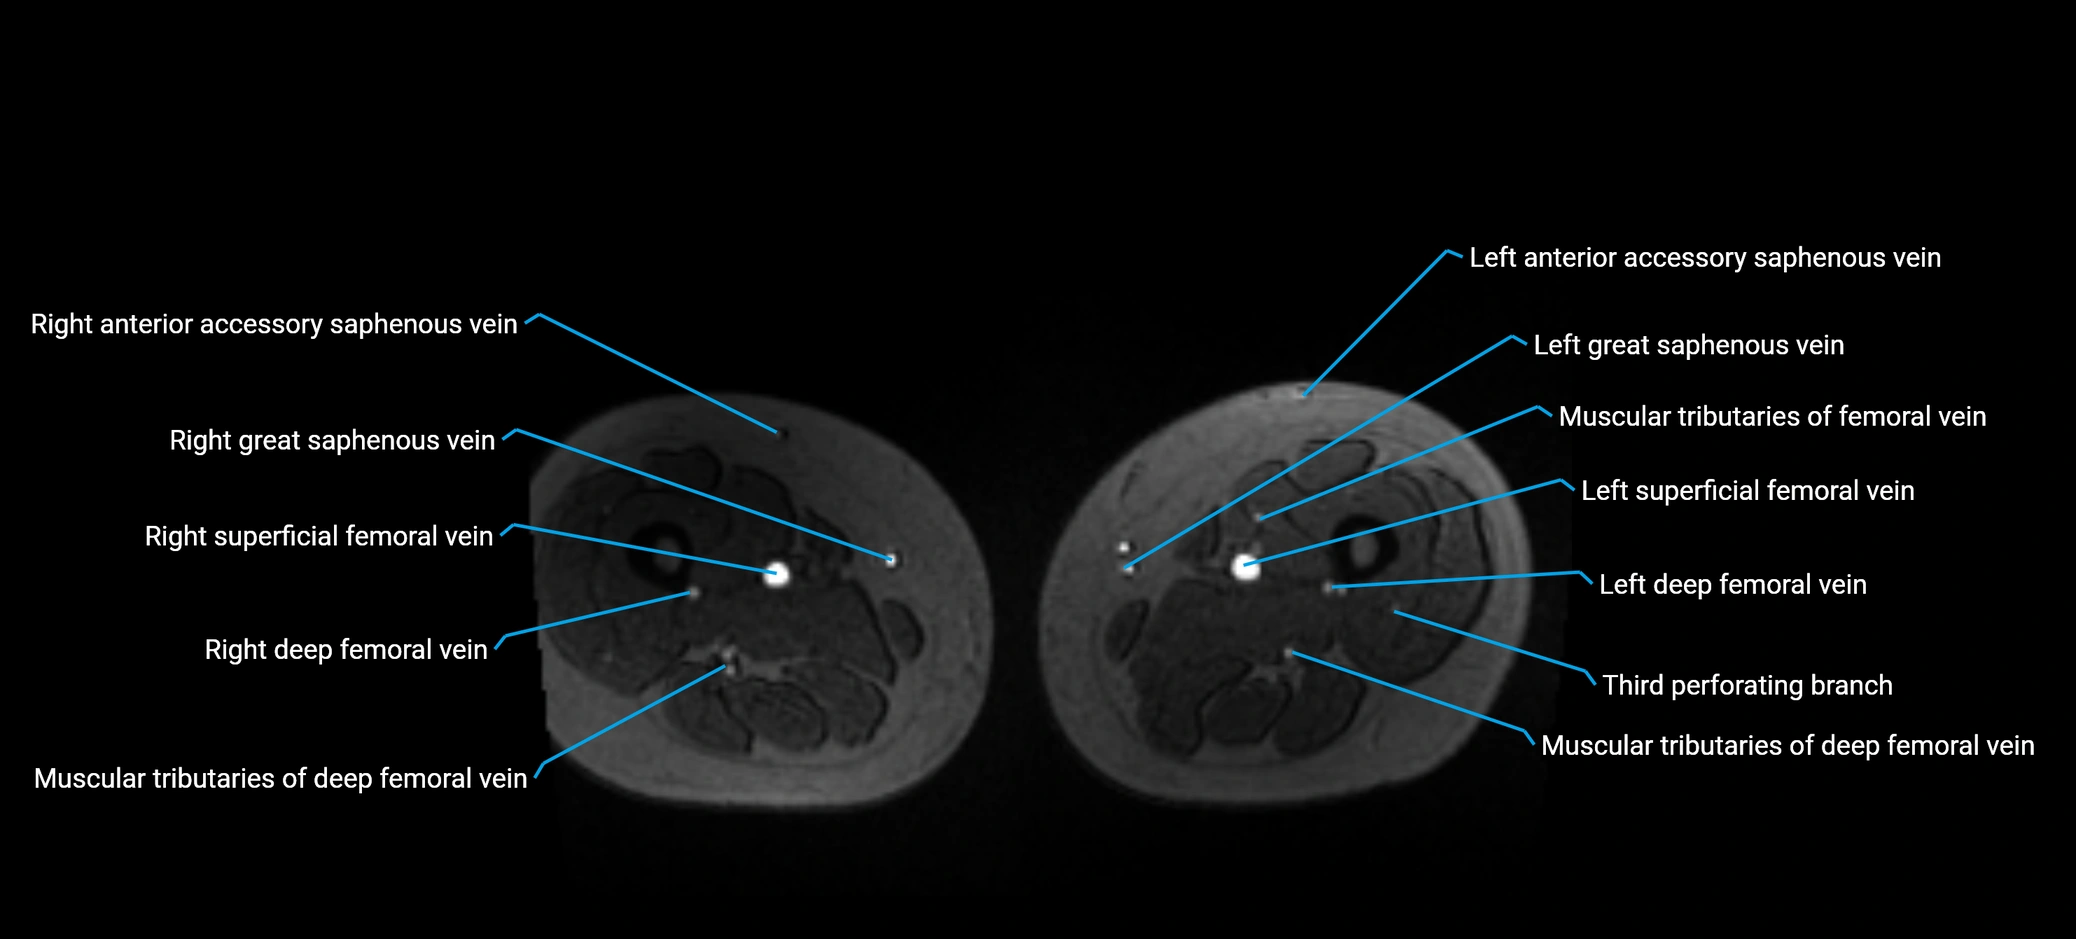

MRI image

image